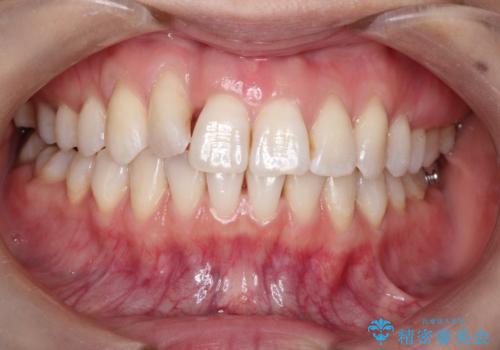

インビザラインによる矯正治療 前歯を整った歯並びへ

- 上の前歯のねじれを気にされて来院されました。

右上の前から2番目の歯が90度近くねじれて並んでいました。

こちらを当初セラミックでの治療をご希望でしたが、セラミック治療の限界と矯正治療のメリットをご説明をさせていただきました。

患者様に考えていただき、矯正治療で前歯をきれいにすることとしました。

インビザラインを使用して矯正することとしました。